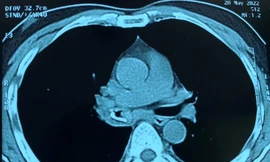

TPO - BV Phổi TƯ vừa cứu sống ca bệnh “Ho ra máu sét đánh”, Đây là chứng bệnh diễn biến rất nhanh sẽ khiến các bác sĩ không kịp trở tay, bệnh nhân giống như kiểu bị cắt tiết gà, máu chảy ra từ động mạch phổi, đóng đông thành từng cục và bít tắc đường thở, chỉ một vài phút sẽ suy hô hấp, trụy tuần hoàn.